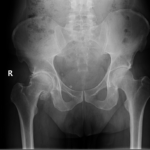

Diagnosis

Diagnosis is made by evaluating medical history, physical examination and X-rays.